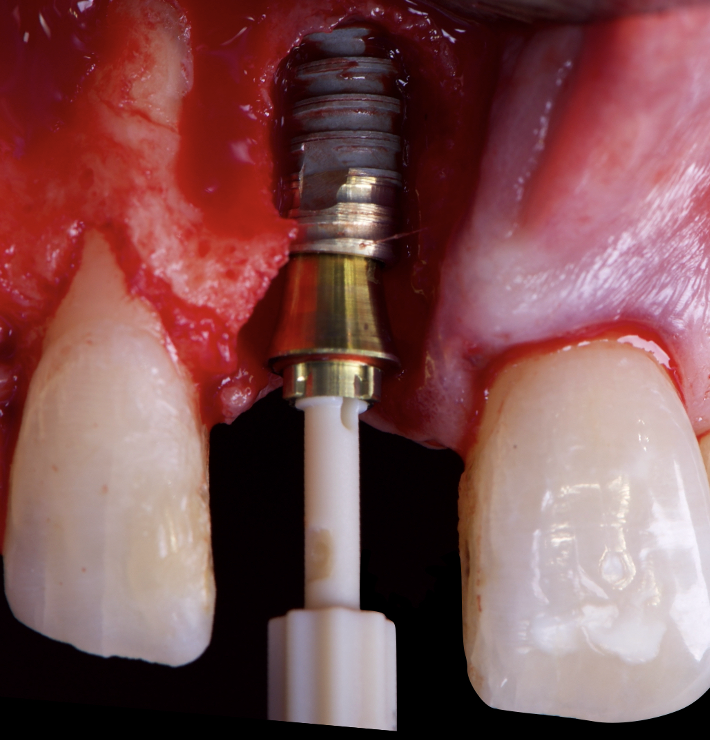

The surgical protocol began with the atraumatic extraction of tooth 1.1 to preserve as much of the alveolar socket as possible. Immediately following extraction, an N1 implant was placed into the socket using a guided surgical approach to ensure ideal three-dimensional positioning. The “one abutment one time” technique was applied to minimize soft tissue manipulation during the healing phase, which is particularly important in esthetic areas.

Given the significant buccal defect, guided bone regeneration (GBR) was performed simultaneously. A mixture of autologous bone and creos™ xenogain™ was applied to the defect and covered with a resorbable creos™ membrane to restore ridge width and support the buccal contour. In addition, a connective tissue graft was harvested and placed in the vestibular region to increase the thickness of keratinized mucosa. This combined approach addressed both hard and soft tissue deficiencies, providing the biological foundation for a stable and esthetic outcome.